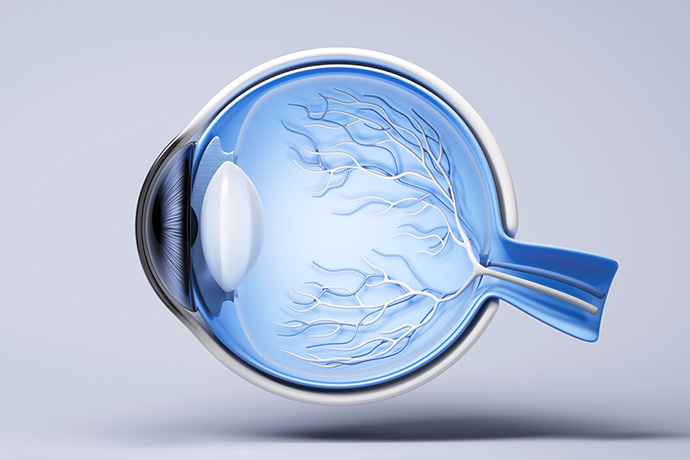

보이는 것 이상의 가치를 전하는,

바로안과의 전문 진료

환자의 눈 건강과 안전을 최우선으로 생각하며,

1:1 맞춤 진료를 진행합니다.

고난도 망막 수술까지 가능한 전문 안과로서,

환자의 눈 건강을 최우선으로 생각합니다.

전문성과 진심이 만난

진료 철학

의료의 본질은 '이해와 신뢰'에 있습니다.

환자분들이 진료 과정을 온전히 이해하고,

치료의 전 과정을 함께 결정할 수 있도록 돕는 것

그것이 바로안과가 추구하는 올바른 진료의 방향입니다.

정확한 진단과 안전한 수술은

첨단 장비에서 시작됩니다.

바로안과는 최신의 장비와 오랜 수술 경험을 기반으로

눈의 상태를 정밀하게 진단하고, 첨단 수술 장비로

안전한 수술을 시행합니다.